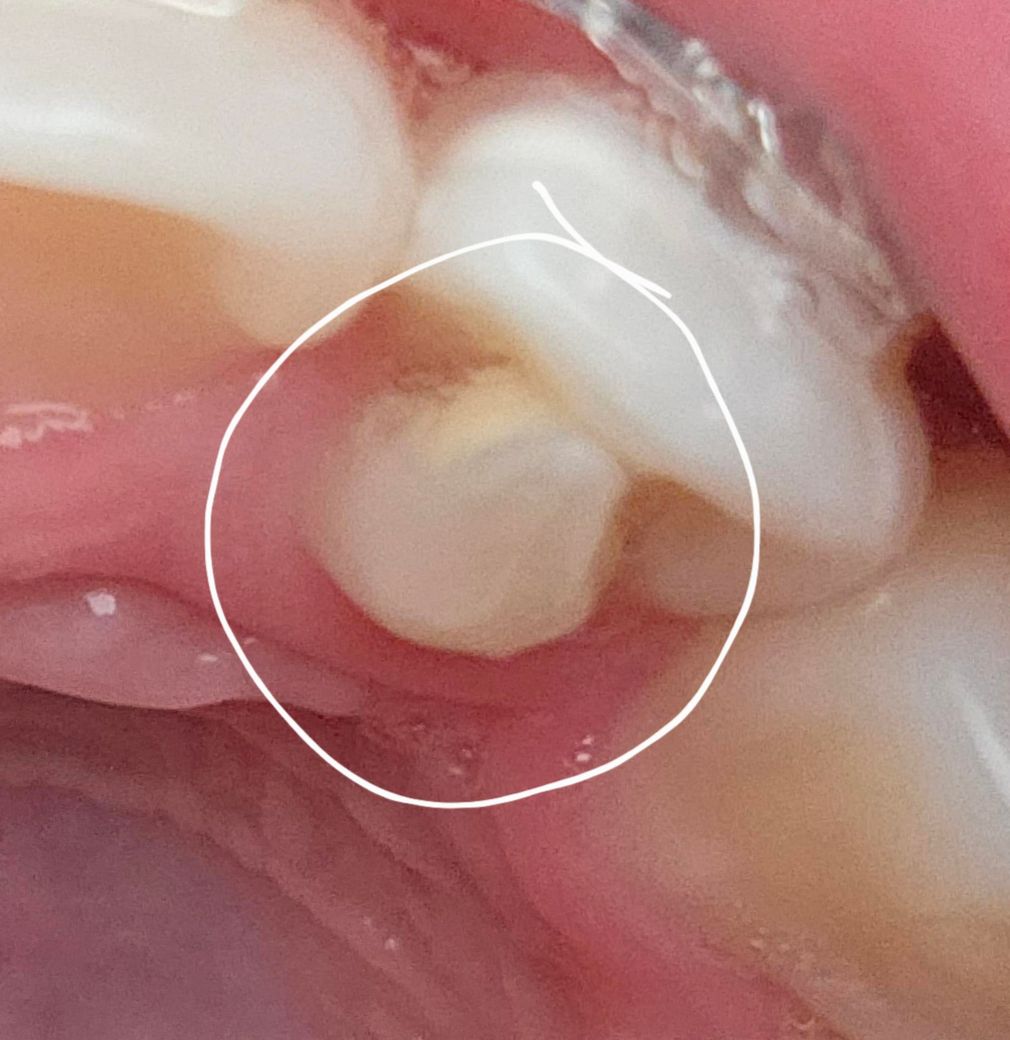

작은 앞니의 표시된 부분은 그대로 두는게 좋을까요?

가끔 아래쪽 작은앞니와 송곳니에 닿아서 아래쪽 치아가 조금 갈린 느낌이 있습니다.

치외치 내지는 과잉치로 보여지는데 맞물리는 치아가 간섭된다면 조치를 취해주는 것이 좋을 것 같습니다.

치아의 돌기로 인해서 교합간섭이 생기거나 불편감이 잇다면 조정을 해주는것이 좋습니다. 그렇지 않았을 경우 치아에 불필요한 힘으로 인해서 손상이나 통증이 생길수 있기 때문입니다.